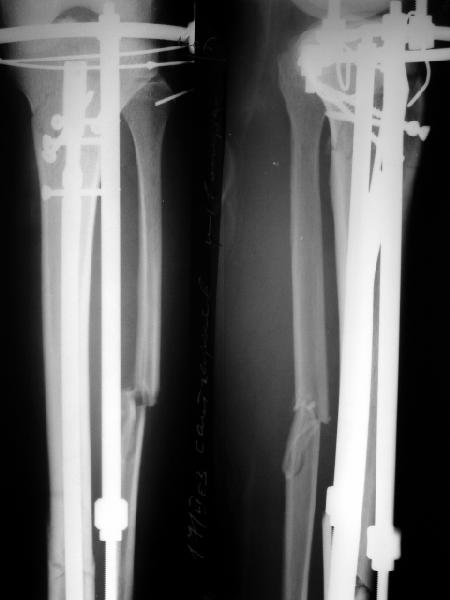

I applied a simple Ilizarov frame, and after reduction inserted a locking screw into a 45 degree hole and two AP screws "miss a nail".

X-rays attached.

Так и сделали. Плюс винт в 45 градусное отверстие и два в передне-заднем направлении. Снимок в приложении выше.